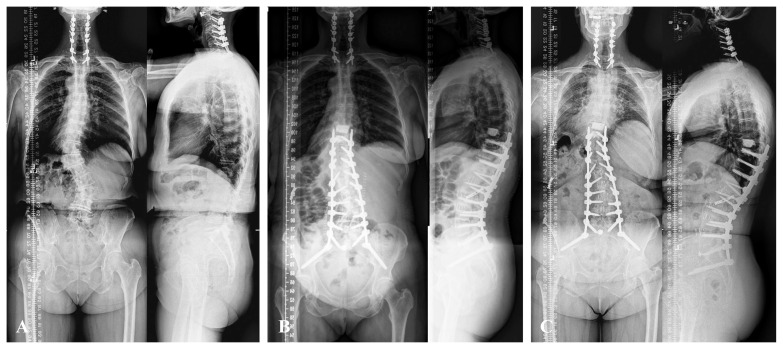

Abstract Image